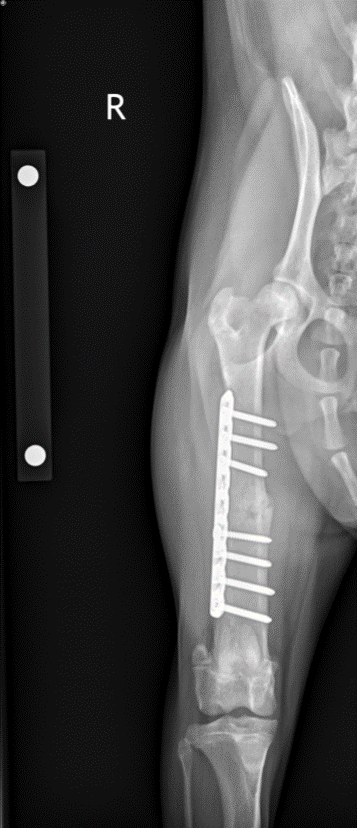

Fracture repairs in dogs involve stabilizing broken bones so they can heal in the correct position and your pet can return to comfortable use of the limb. Depending on the fracture, this may be done with bone plates and screws, pins, or wires that hold the pieces together while they heal. Our goal is to restore normal function, minimize pain, and reduce the risk of long‑term problems like arthritis or deformity.